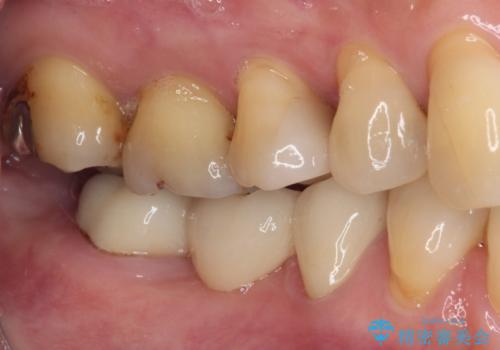

前歯のみならず、奥歯の銀歯や下顎前歯のデコボコなど、色々と気になる部分を治したいとのことでした。

下顎と上顎臼歯部については矯正治療を行い、奥歯の欠損部位はオールセラミックブリッジを、その他の銀歯はセラミックインレーなどにより治療を行うこととしました。